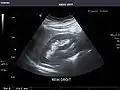

Spleen

Spleen: Normal in size.